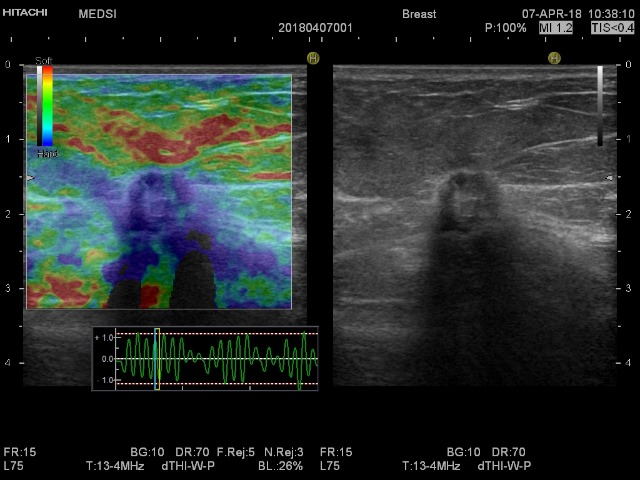

Эластография помогает, но в данном случае не сильно.

Показана кор-биопсия, даже если бы эластография была другой.